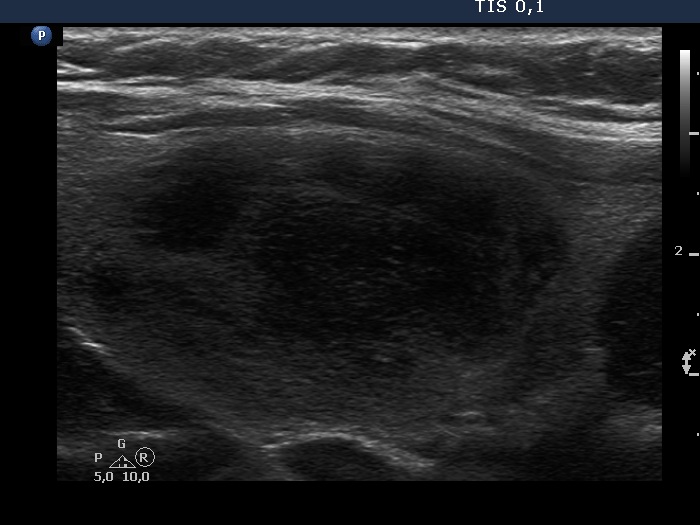

Second examination 3 years later (second, fourth and sixth rows of images):

Ultrasonography. Compared with the previous examination, both the number and the size of discrete lesions in the thyroid have increased.